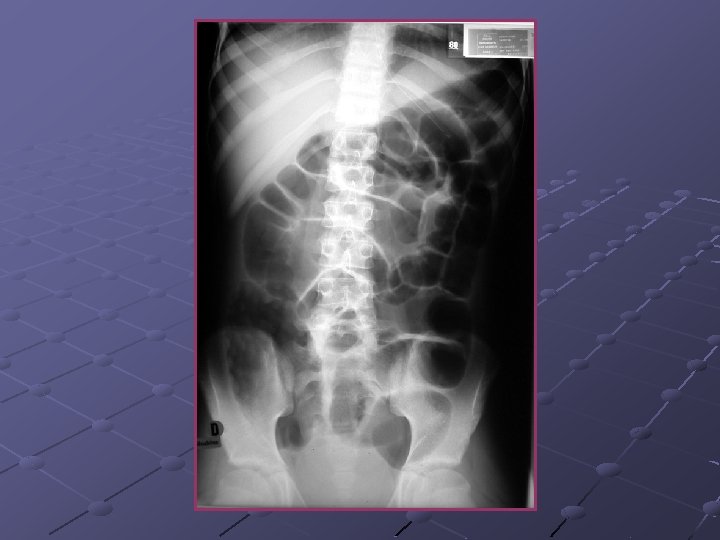

Cas n° 3 Garçon de 19 ans Pas d’antécédents particuliers Douleurs et distension abdominales, vomissements Examen distension diffuse, pas de signes de péritonite

« northern exposure sign » « coffee bean sign »

Volvulus du colon sigmoïde Cause fréquente de volvulus( segment long et mobile) ASP couché ( « coffee bean sign » ) pose le diagnostic dans 80% des cas Origine congénitale ou défaillance des moyens de fixité du colon ttt: décompression endoscopique suivie d’une résection élective